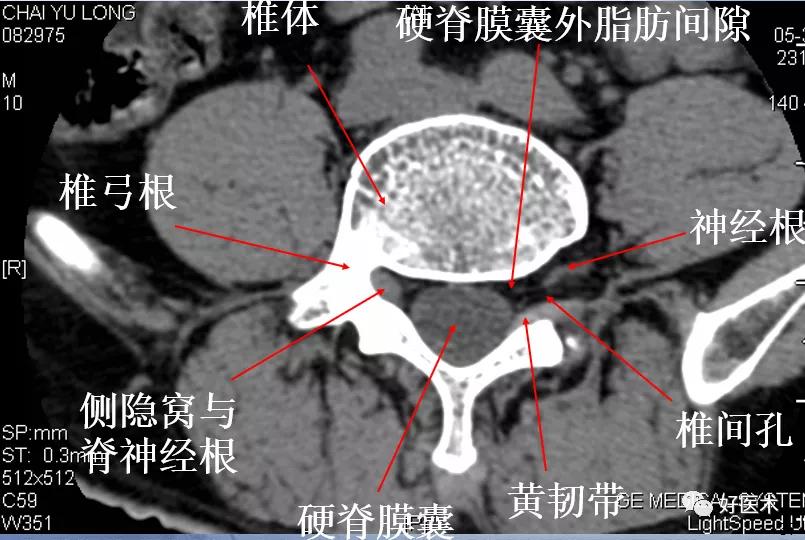

- 椎间孔前为椎体,后为椎小关节,上下为椎弓根,内与侧隐窝相连,有脊神经根通过;

- 侧隐窝:向下外续于椎间孔,有脊神经经过 –前壁为椎体后外缘 –后壁为上关节突前面与黄韧带 –外界为椎弓根;

- 正常前后径为3-5mm,<3 mm侧隐窝狭窄,>5mm,不狭窄。

2.椎间盘及其附件的解剖结构:

- 椎体:L1 ~L5 体积递增

- 椎弓根:比胸椎长和宽,椭圆形

- 棘突:水平,方形

- 横突:比胸椎小

- 椎间孔:大,但神经根受压风险增加

- 椎孔:大得能够容纳马尾和神经根

腰段椎管的形状:从上而下为卵圆形----三角形---三叶形